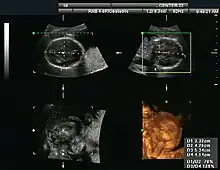

Obstetrical sonography was originally developed in the late 1950s and 1960s by Sir Ian Donald[19][20] and is commonly used during pregnancy to check the development and presentation of the fetus. It can be used to identify many conditions that could be potentially harmful to the mother and/or baby possibly remaining undiagnosed or with delayed diagnosis in the absence of sonography. It is currently believed that the risk of delayed diagnosis is greater than the small risk, if any, associated with undergoing an ultrasound scan. However, its use for non-medical purposes such as fetal "keepsake" videos and photos is discouraged.[21]

Obstetric ultrasound is primarily used to:

- Date the pregnancy (gestational age)

- Confirm fetal viability

- Determine location of fetus, intrauterine vs ectopic

- Check the location of the placenta in relation to the cervix

- Check for the number of fetuses (multiple pregnancy)

- Check for major physical abnormalities.

- Assess fetal growth (for evidence of intrauterine growth restriction (IUGR))

- Check for fetal movement and heartbeat.

- Determine the sex of the baby

3-D images can be generated by acquiring a series of adjacent 2-D images. Commonly a specialized probe that mechanically scans a conventional 2-D image transducer is used. However, since the mechanical scanning is slow, it is difficult to make 3D images of moving tissues. Recently, 2-D phased array transducers that can sweep the beam in 3-D have been developed. These can image faster and can even be used to make live 3-D images of a beating heart.